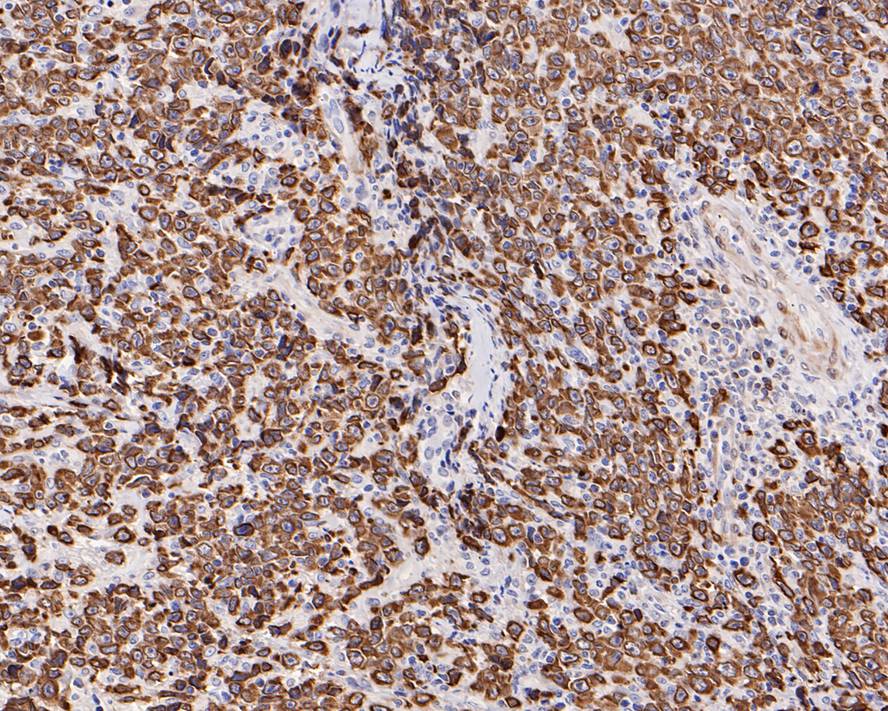

Immunohistochemical analysis of paraffin-embedded human B-cell lymphoma tissue with Rabbit anti-Bcl-2 antibody (HA721235) at 1/1,000 dilution.

The section was pre-treated using heat mediated antigen retrieval with Tris-EDTA buffer (pH 9.0) for 20 minutes. The tissues were blocked in 1% BSA for 20 minutes at room temperature, washed with ddH2O and PBS, and then probed with the primary antibody (HA721235) at 1/1,000 dilution for 1 hour at room temperature. The detection was performed using an HRP conjugated compact polymer system. DAB was used as the chromogen. Tissues were counterstained with hematoxylin and mounted with DPX.